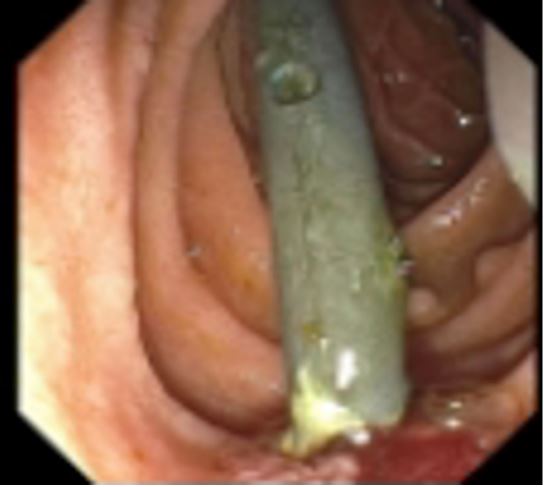

The patient was brought in for an emergent repeat ERCP. During the procedure, it was noted that the distal tip of the biliary stent had invaginated into the lateral wall of the duodenum or possibly extraluminal in the retroperitoneal space (Figures 1-3). Patient was then admitted, and general surgery was consulted. He was taken to surgery where it was confirmed that the single pigtail biliary stent had eroded through the duodenum. Procedures performed during surgery included a bile duct exploration, cholecystectomy, choleoducoduodemostomy, and duodenal repair. Patient was treated with intravenous Zosyn while hospitalized. Post operatively the patient responded well with routine post operative care, antibiotics, and fluids.

Figure 1: ERCP image of Biliary stent coming out of ampulla and invaginating into the opposite duodenal wall.

Figure 2: ERCP showing biliary stent invaginating through duodenal wall, opposite Ampulla.